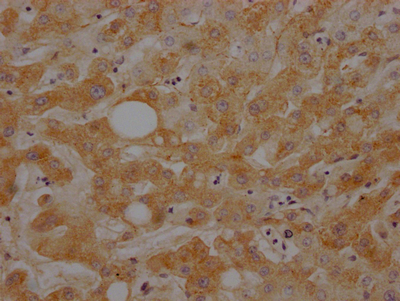

IHC image of CSB-RA303909A0HU diluted at 1:100 and staining in paraffin-embedded human liver tissue performed on a Leica BondTM system. After dewaxing and hydration, antigen retrieval was mediated by high pressure in a citrate buffer (pH 6.0). Section was blocked with 10% normal goat serum 30min at RT. Then primary antibody (1% BSA) was incubated at 4℃ overnight. The primary is detected by a Goat anti-rabbit IgG polymer labeled by HRP and visualized using 0.05% DAB.